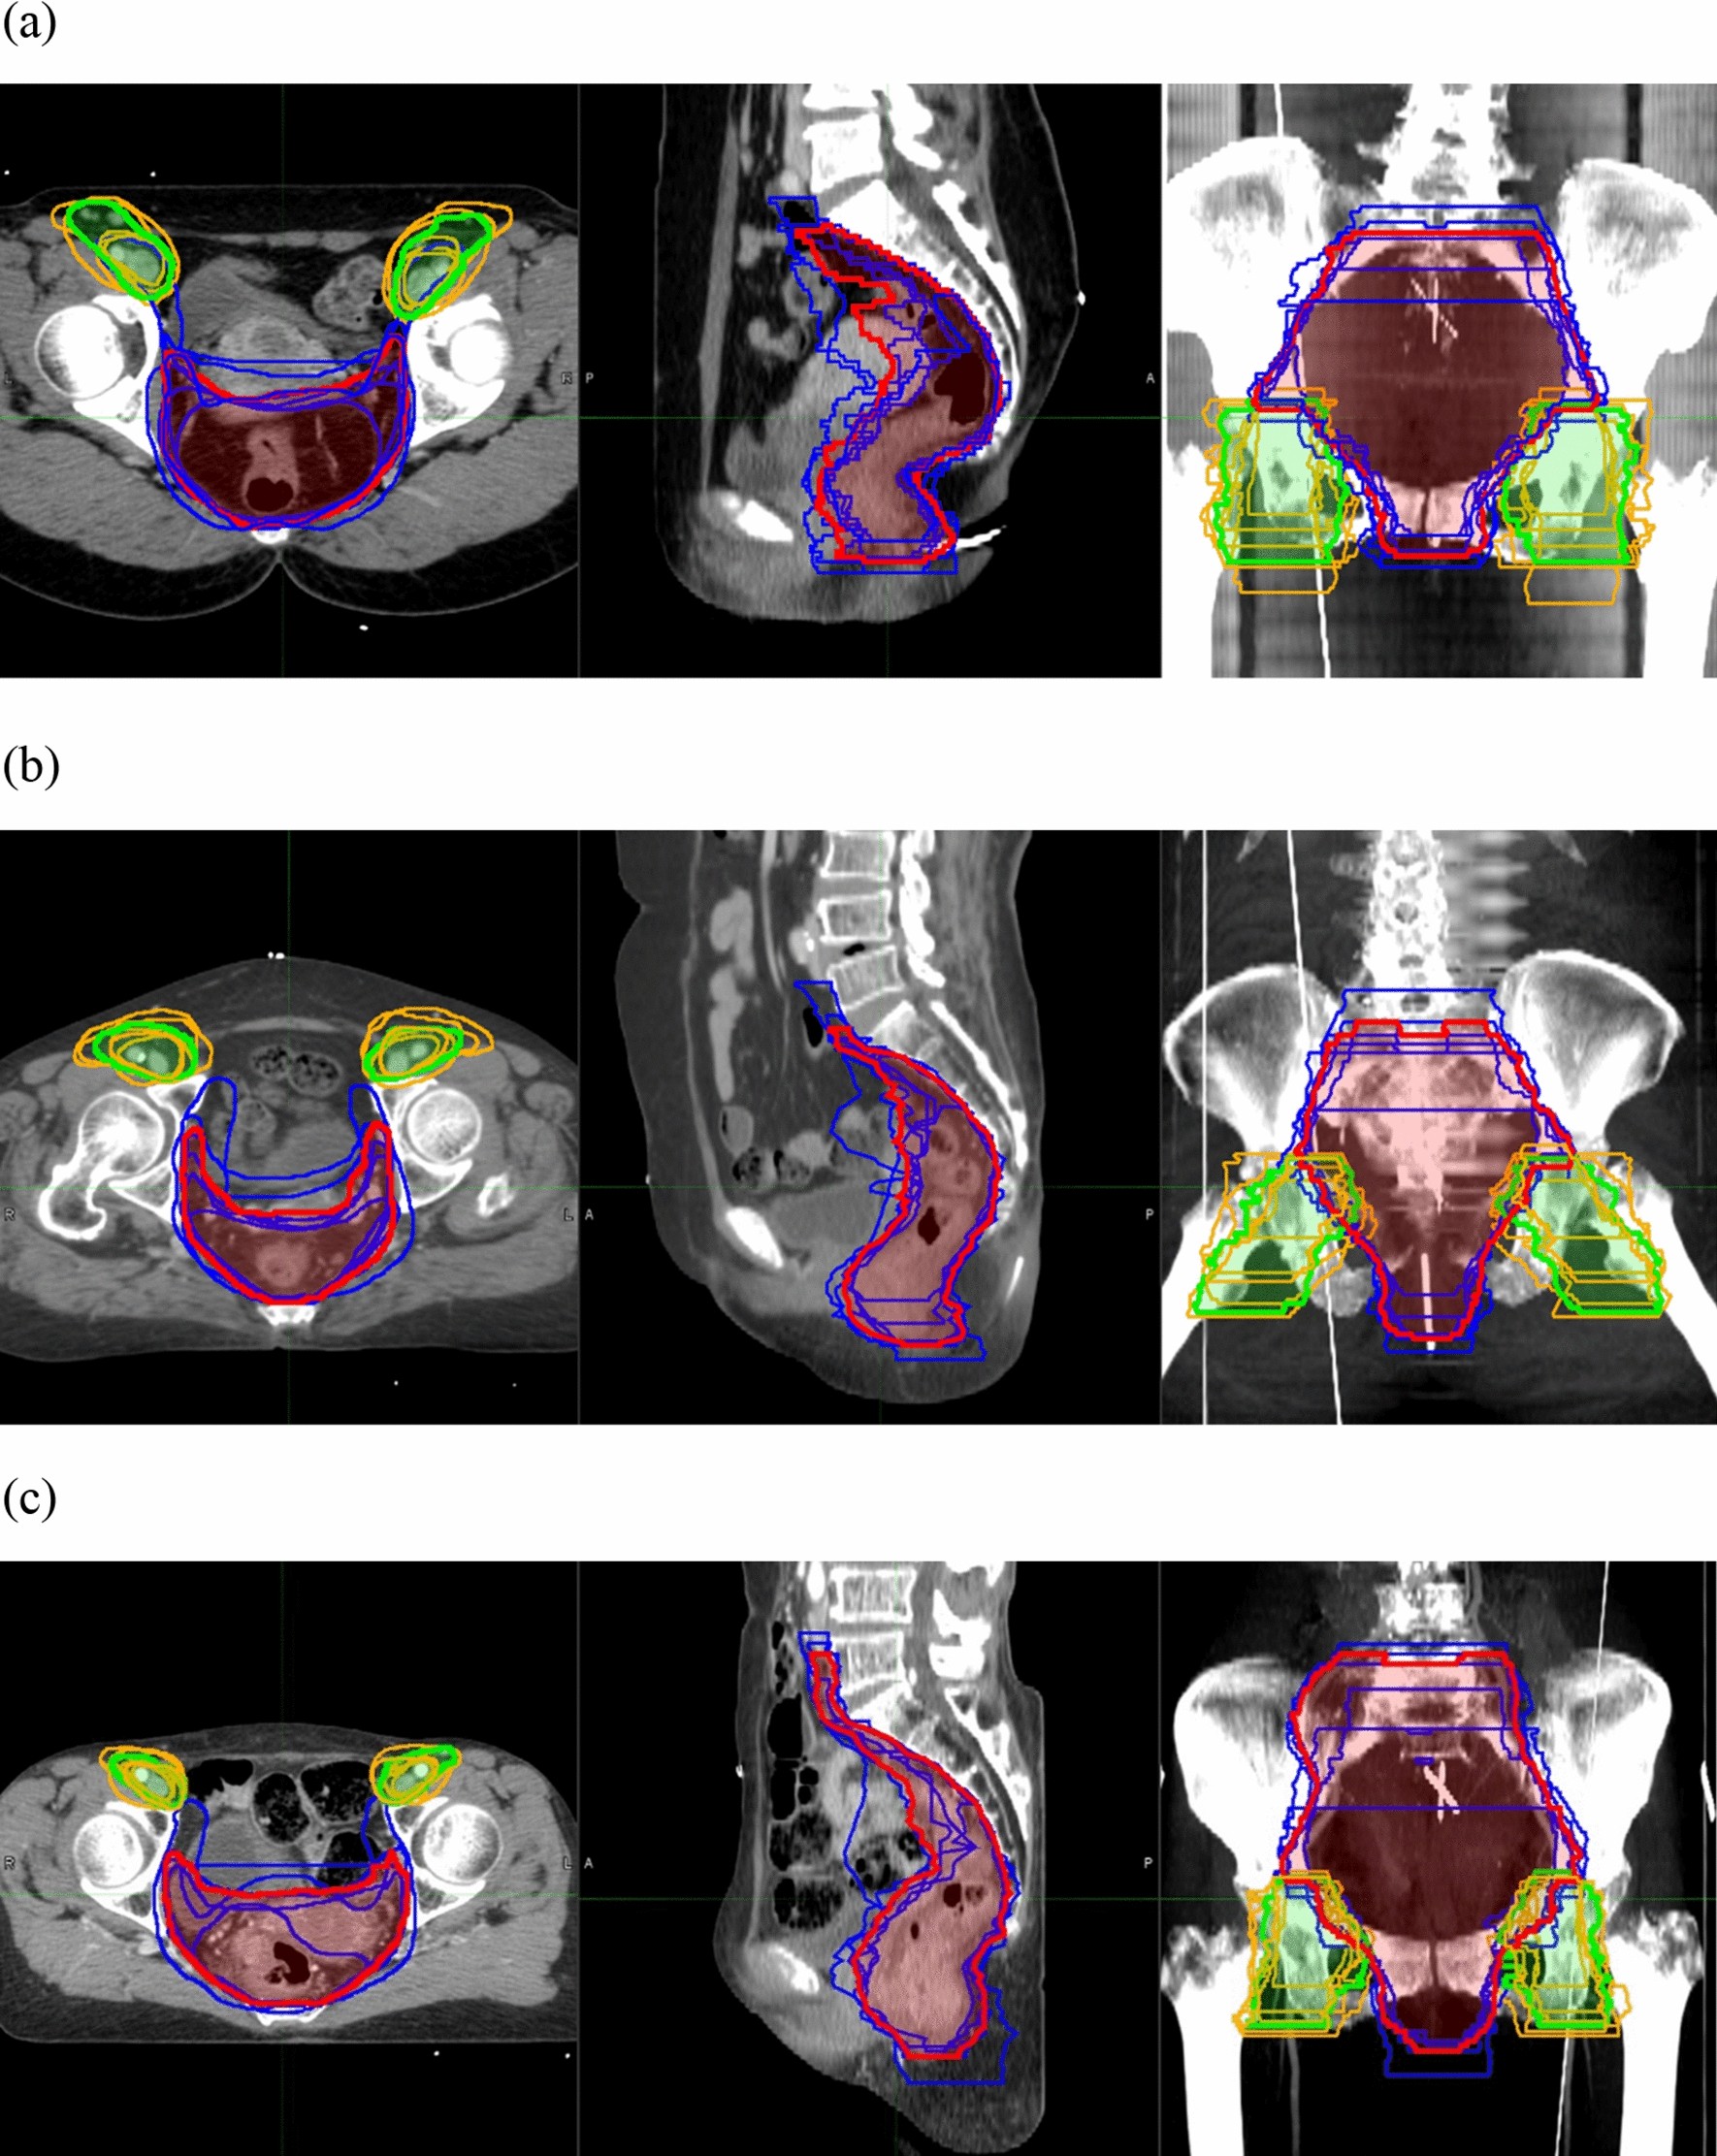

Figure 1

From: Interobserver variability in clinical target volume delineation in anal squamous cell carcinoma

CTV-pelvis (dark blue) and CTV-inguinal (orange) of 7 radiation oncologists and STAPLE generated contour of CTV-pelvis (red) and CTV-inguinal (green) with confidence level of 80%. (a) Patient 1; (b) Patient 2; (c) Patient 3. Figures were generated using MIM 6.9.7 (MIMVista Corp, Cleveland, Ohio).